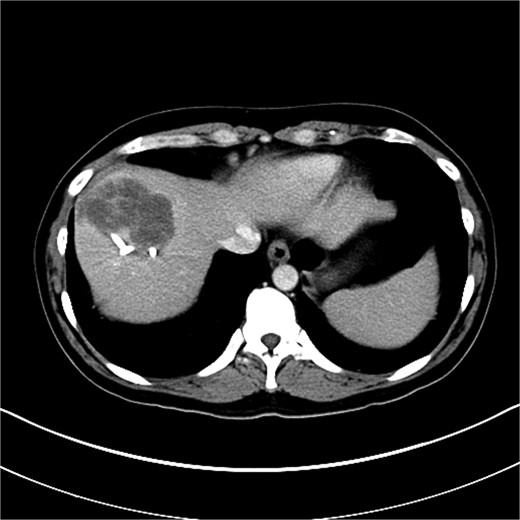

Upon admission to the GI ward, a repeat abdominal CT scan suggested a possible liver abscess. Drainage was performed on September, 2024, and empirical antibiotic therapy with ceftriaxone and metronidazole was initiated. Despite initial drainage and antibiotics, the patient continued to experience intermittent fever. A subsequent CT scan revealed a heterogeneous lesion measuring ~7.5 × 8.5 cm at S8 (Figs 2 and 3). A sono-guided liver biopsy was performed, and the pathological report indicated hepatic sarcomatoid carcinoma with variable positivity for CK and CK7, and negativity for CK20, glypican-3, ERG, and CD34 stains, suggesting a possible cholangiocarcinoma component. A general surgery (GS) consultation was obtained for suspected liver tumor management.

An 8.0 × 8.0 cm sarcomatoid carcinoma of the liver at S8 with direct invasion into the diaphragm and RLL was identified.